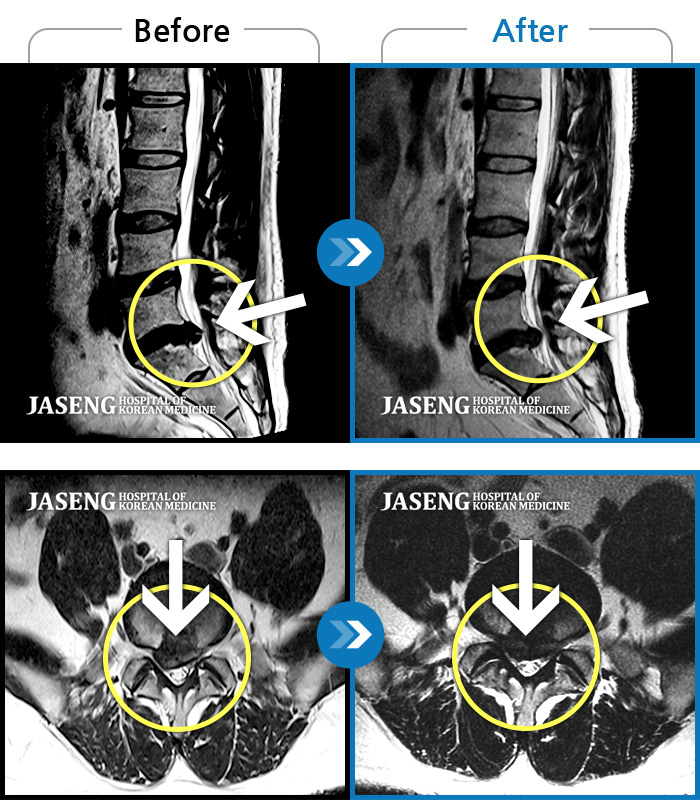

Before

After

환자에게 사전 동의를 받아 동일 조건에서 촬영되었습니다.

개인에 따라 치료 후 부작용이 발생할 수 있으니 의료진과 상담 후 치료를 진행하시기 바랍니다.

수개월간 지속된 허리 통증이 악화

허리숙이는 일을 한 후 급격하게 발생한 우측하지 방사통, 보행장애, 야간통이 있었다.